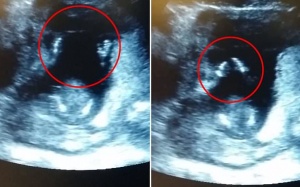

Mang thai là thời gian được cho là hạnh phúc nhất nhưng cũng đáng sợ nhất cuộc đợi người phụ nữ bởi những thay đổi về tâm sinh lý, những rủi ro khi vượt cạn, đặc biệt là...